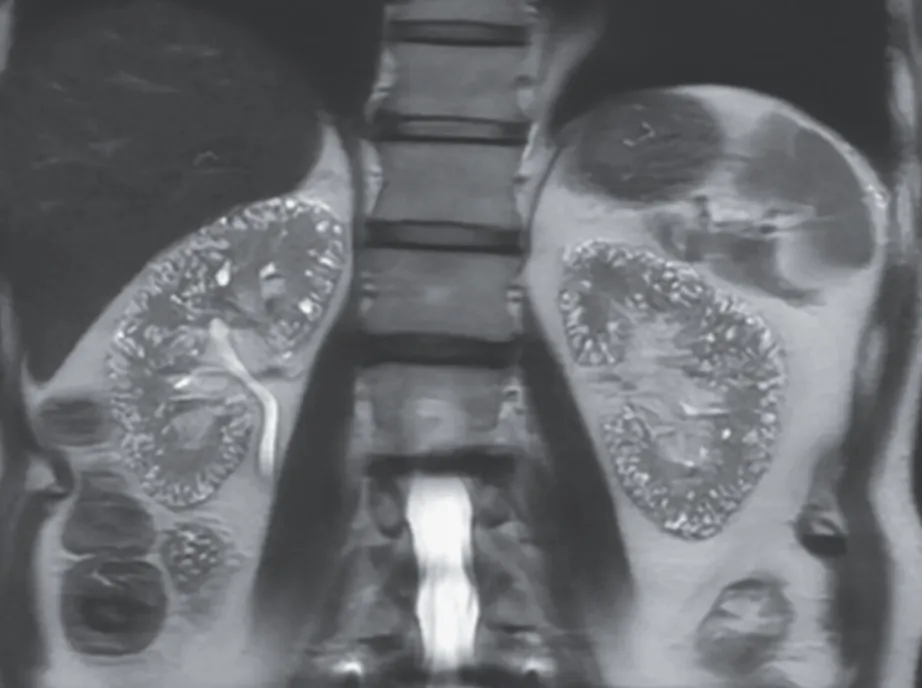

Uma causa incomum de hematúria glomerular intermitente!

Uma causa incomum de hematúria glomerular intermitente!

Hematúria pós infecção, caso clínicos para auxiliar no entendimento de causas glomerulares comuns e raras...